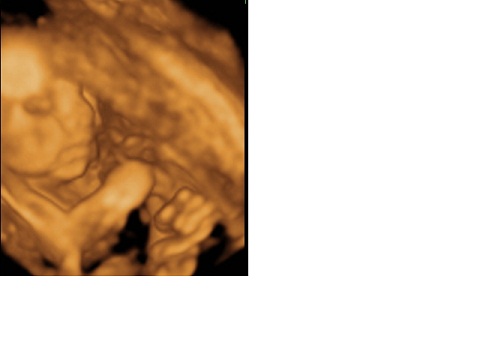

Szóval budapesti vagyok, hosszú közdelmes hónapok után (műtét, vizsgálatok, hormonok, és stb) az első inszeminációra jött össze Bálint. Én kezdetektől fogva nem dolgozom, mert óvó néni vagyok, és ez fizikailag is sok, de fertőzések miatt a dokim úgy gondolta ne erőltessük. Igaz a tanévet befejeztem, utána nekünk jött a nagy nyári szünet, és így csak szeptembertől nem vagyok hivatalosan bent. Mkinden eddig zökkenőmentesen megy, és így is fog haladni január 12-ig. Bálint szépen fejlődik 717g, és nagyon helyes 4D képeink vannak róla.Valószínűleg programozott császárral fogok szülni a eddig felmerült dolgok miatt( Bálint feje nagyon kerek :D , az elősző műtét, ami egy laporoszkópia volt a köldököm nem gyógyult be teljesen, így bent is lehetnek ilyen problémák, és régen HPV-s voltam)

majd mutass 4d-s képeket ha tudsz.szeretünk gyönyörködni a babaképekben :)

Én eddig azért nem regisztráltam, mert az első 12 hétben nem mertem, mert így is zötyögős volt a dolgo, de inkább féltem kimondani. Utána jött a nyár ér meg minden fele, ahol csak 3G-n tudtam olvasni a topikot, és akko rám 20 hetesen , amikor újra gép előtt voltam, már annyira összeszokottnak látszott a dolog, hogy úgy éreztem jó így. De most meg így jó, változnak az idők :D Kép

Most megpróbáltam Bálintról feltötlteni képet, ha nem sikerült volna, kérek egy kis segítséget

Megpróbálom nagyobba felrakni Bálintot: Kép Bálint 24 hetes 2 napos